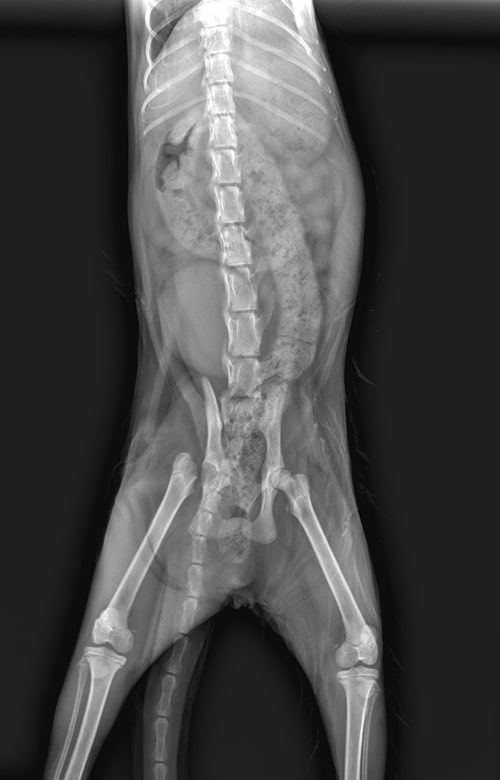

X-rays are a vital diagnostic tool for assessing bones, joints, the chest, abdomen, bladder, and other internal structures. Our mobile hospital is equipped with X-ray technology that delivers high-quality images with minimal radiation exposure. Our veterinarians can interpret initial results on-site and may consult with a radiology specialist for expert review when needed.

A Siamese cat sits on a table next to a laptop displaying an X-ray of a cat's head and neck, as a veterinarian examines the results in what appears to be a veterinary clinic. X-ray image of an animal, likely a dog, viewed from above, showing the spine, ribs, pelvis, and leg bones; some internal organs are faintly visible—often used by a veterinarian or mobile vet for diagnostic purposes.